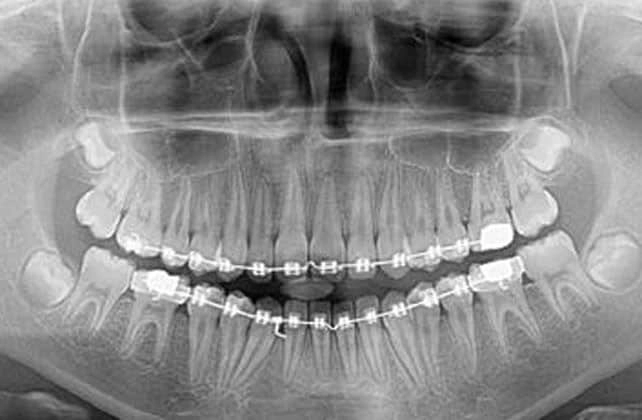

رادیوگرافی بایت وینگ

رادیوگرافی بایت وینگ BW رادیوگرافی بایت وینگ در گذشته پزشک معالج برای اینکه به بیماریها بیمار پی ببرد به چهره چشمی عمل میکرد, که البته بسیاری از بیماری ها به چهره پنهان باقی میماند و دشواری ها زیادی را بوجود می آورد. با ترقی تکنولوژی کل چیز تغ…